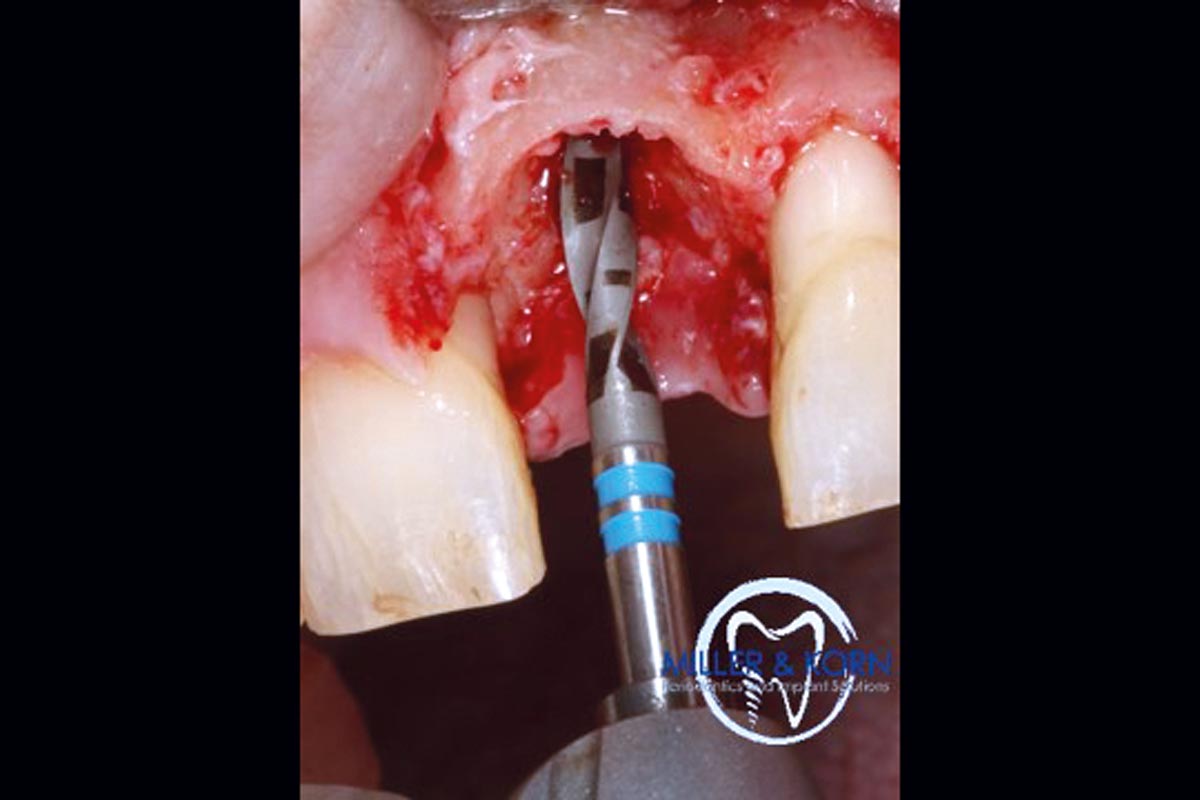

10/39 - Pilot drilling with a 2.2 mm twist drillImmediate implant placement and correction of horizontal and vertical bone loss using an allograft bone ring, cerabone® and Jason® membrane - Drs. Miller and Korn